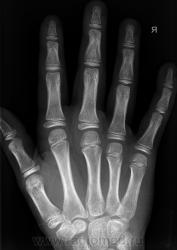

Остеоэпифизеолиз о/ф III пальца.

Спасибо Валентин Львович за обработку изображений, в данном случае остеоэпифизиолиз проксимальной фаланги 3п.. В косой проекции кстати даже четко видно ступеньку.

Снимок сделан вчера вечером по дежурству, на Omni-Diagnost(philips).